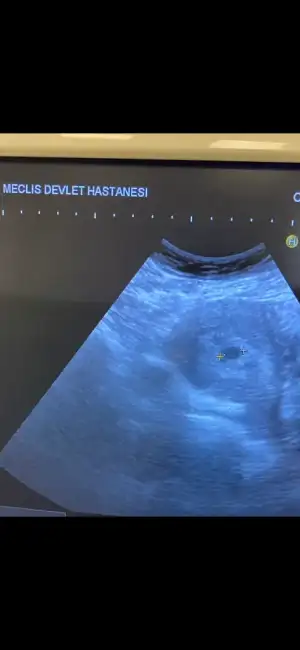

Kızlar ben 2 gün arayla kan verdim 29 126 260 659 çıktı 659 dam 2 gün sonra keseyi gördüm . Doktor kese çok güzel rahim duvarı çok kalın rahimin en üstüne yerleşmiş dedi 659dan 8 gün sonra doktor çağırdı değerim beta10.000 çıktı doktor kese güzel gelişmiş 12.4 mm dedi. Ben yerimde duramadım 4 gün sonra başka doktora randevu aldım. Doktor karındna baktı kese 17 mm yolk sac var embriyo da var kalp atımı yeni başlamış henüz yavaş dinlenemez dedi vajinal ultrasonla baktı daha net görmem gerekirdi dedi ama göremiyorum dedi. Karındna daha net gördğm dedi. Tabi benden bir sürü kan almış beta 10.000 den 4 günde 29.000 olmuş. Çok az artmış gibi geldi hemen akşam acilde özele gittim dedi ki belli haftadan sonra 2 günde 2 kat değiş 3-4 günde 2 kat artar dedi . Progesteren değerim 10 çıkmış çok düşük değil mi diyorum bence yeterli dedi. Vajinal muayene etti kese şu an boş ama henüz yorum yapmak için erken dedi. Ama kesenin şekli tam yuvarlak değil dedi kese istediğim gibi değil dedi düzelir diye düşünüyorum dedi karından bakmasını rica ettim sadece yolk sac gördü bu arada 6+0ım. Yerimde duramıyorum bu gebelik sağlıksız mı? Sabah gittiğim doktor kesenin hakkında kese iyi yerleşimi iyi rahim ağzı Kapalı rahim kalınlığı iyi dedi akşam özele gittim şekli fasülye gibi dedi. Sabahkinden ultrason kağıdı istedim ekranı kapattım dedi özeldeki verdi. Allah rızası için bilen birisi bir şeye desin. Doktorlar neden aynı fikirde değil. Progesteron değerim çok mu düşük beta son artışta az mı artmış bu gebelik sağlıksız mı ? İlk gittiğim ultrason 5+2 başka doktor (yuvarlak olan)

Diğeri 6+0 başka doktor kese şekli tam yuvarlak değil diyen . Geceden beri hiç uyuyamadım. Gözümü kapattım bu olay açtım bu olay. Bana bir fikir verin zaten 3 kaybım var bu 4. Olsun istemiyorum

Merhaba özeldeki doktora asla hakkımı helal etmiyorum 3 gün sonra devlete gittim. Ultrasonla baktı kesem yuvarlak, kalp atışı başlamış. Şöyle anlatayım

Son adet tarihime göre 6+0 da özelde doktora gittim kesen fasüleywye benziyor içi bomboş dedi 6+6 çıktı dedim ki daha önce yolk ve bebek göründü şimdi boş diyorsunuz dedim zorla baktı 10 dk da yolk kesesini zor gördü. Ama bebek imkansız dedi ısrarla kesenin şekli bozuk dedi neyse 3 gün sonra gittim devlete kesenin şekli yerleşimi iyi 6+3 çıktı (sat uyumlu) bebek kalp atışı var. Durumu devletteki doktora anlatınca tecrübesilziktendir dedi